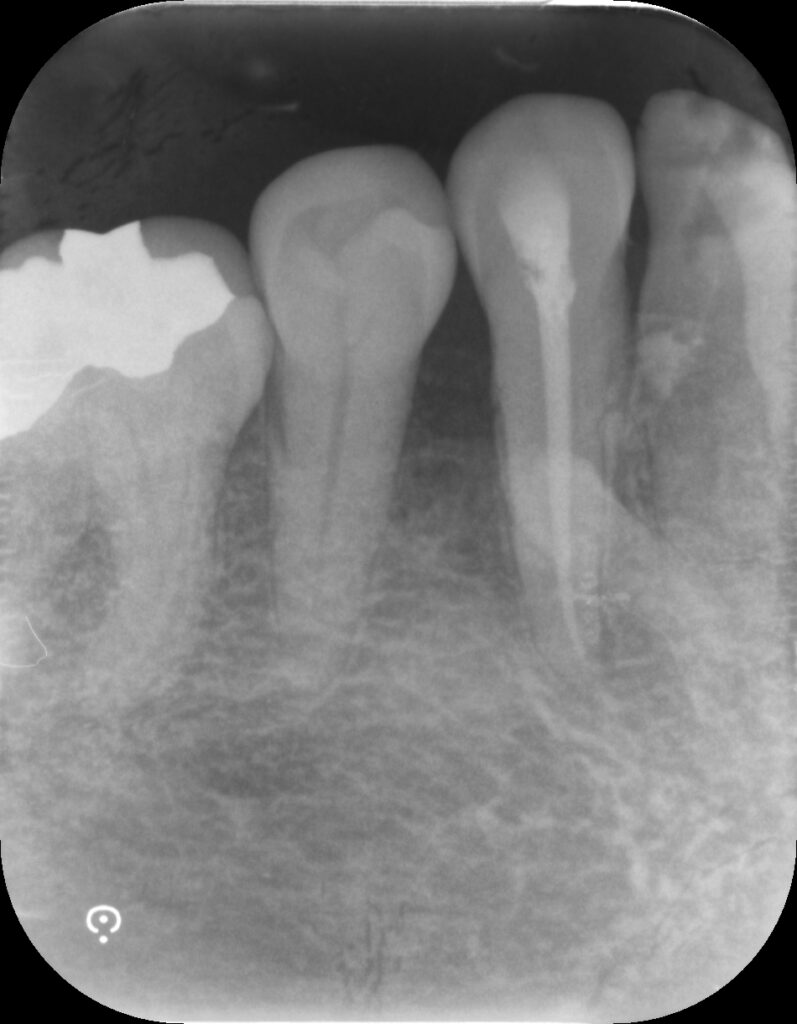

根管治療が終了した歯には、再び歯の中で細菌感染が起きないように根管内を封鎖します。

レントゲンを見ると根管内が白い材料で満たされているのが分かるかと思います。

適切な治療をおこなうことで、このようにプローブが深く入らなくなり、出血も無くなります。

引き締まった歯肉見るとテンション上がります!